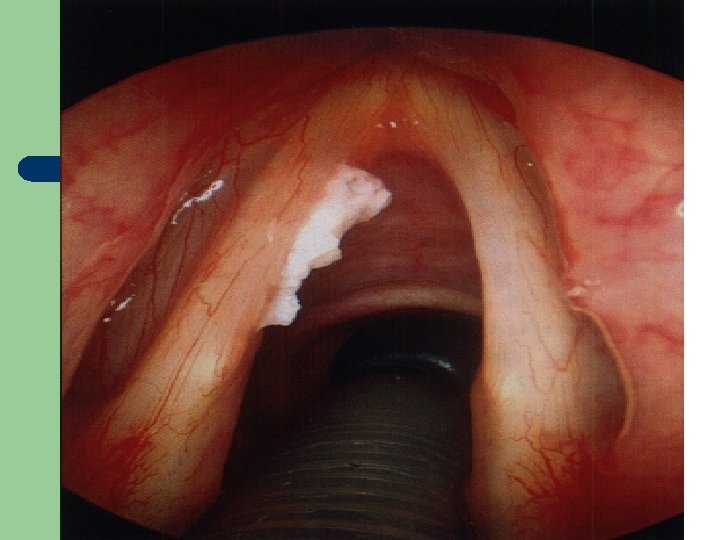

Vývoj dětské chraptivosti l 1. 2. 3. 4. Průvodním jevem při dětské chraptivosti je pokašlávání a pochrchlávání. Nález na hlasivkách postupuje takto: Hyperemické (překrvené hlasivky, Hypertrofické, vřetenovité zduření, hlasivkový uzávěr je neúplný a hlas má dyšnou příměs, ventrikulární řasy se začínají vyklenovat Zpěvácké uzlíčky, nejčastěji na hranicích přední a střední třetiny hlasivek Atrofie hlasivek až s podélnou rýhou, při fonaci nedomykavost uzávěru.

Hlasivkový uzlík l

Hlasivkový uzlík l

Hlasivkové uzlíky l